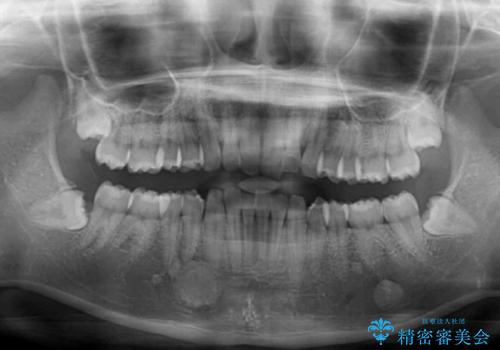

デコボコと深い咬み合わせの改善 インビザラインによる矯正治療

- 口元のデコボコと深い咬み合わせ(ディープバイト)を気にして来院された患者様です。

インビザラインによる上下歯列の拡大と、IPR(歯と歯の間を削る)にるスペースの獲得により、口元のデコボコとディープバイトを改善することとしました。